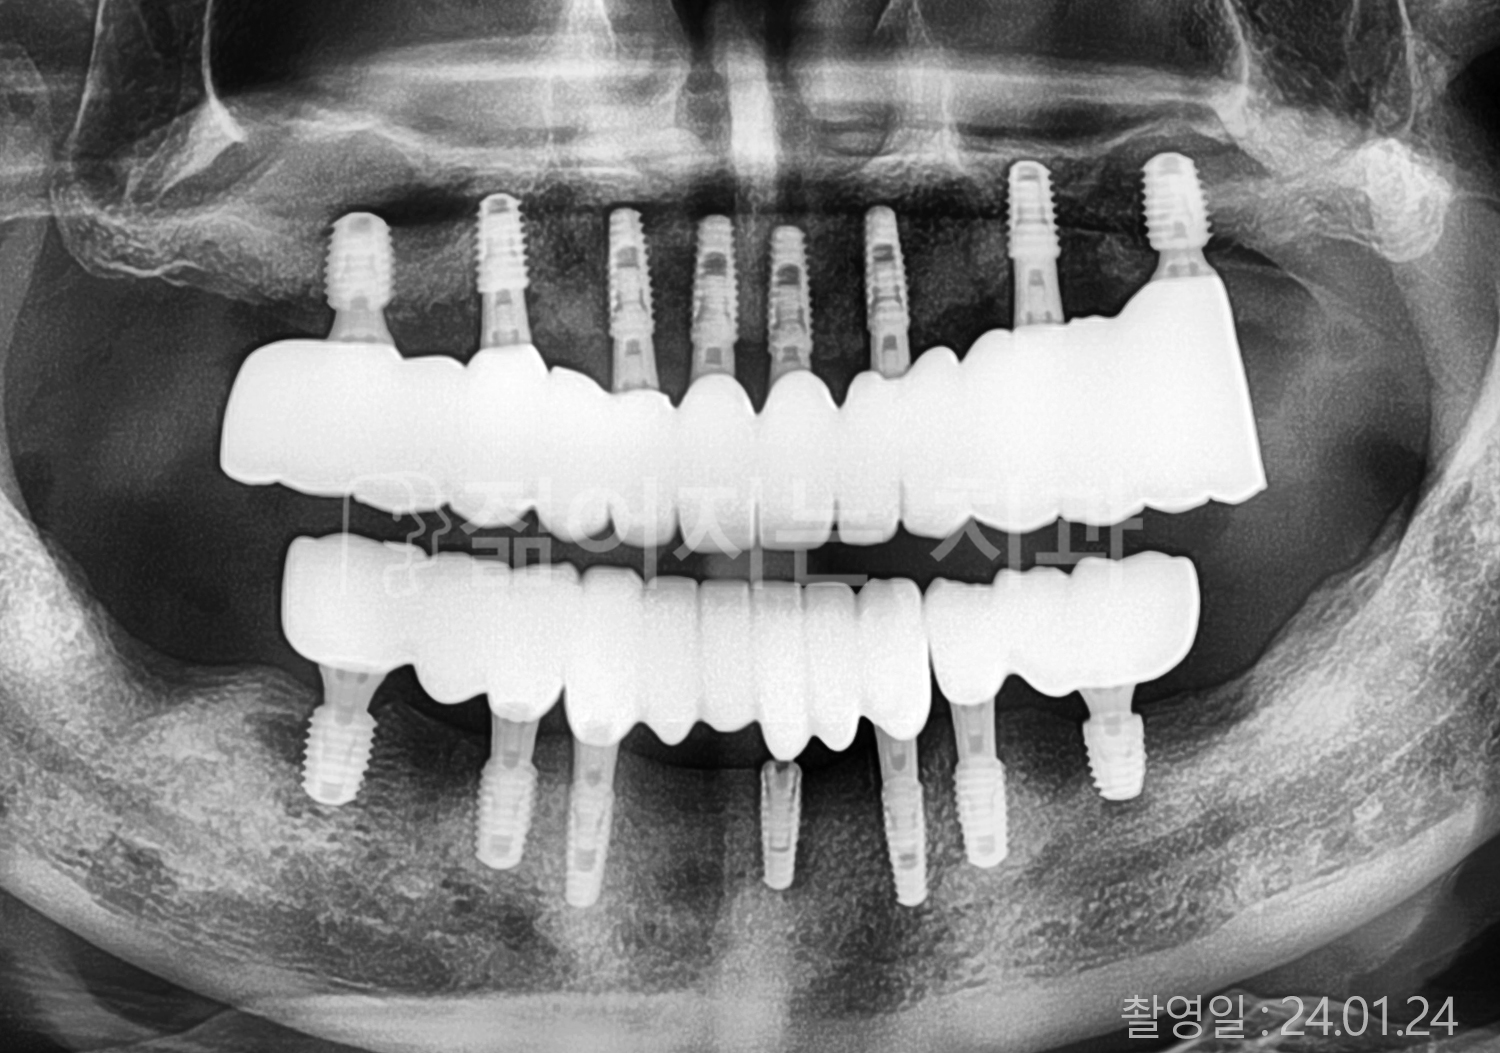

• 60대 전체치아 10개 이상 임플란트

• 50대 전체치아 10개 이상 임플란트

• 70대 고혈압, 암, 갑상선 질환 전체치아 10개 이상 임플란트

• 60대 고혈압, 당뇨, 고지혈증 전체치아 10개 이상 임플란트

• 40대 당뇨 전체치아 10개 이상 임플란트

• 70대 전체치아 10개 이상 임플란트

• 60대 당뇨 전체치아 10개 이상 임플란트

• 70대 고혈압, 당뇨 전체치아 10개 이상 임플란트